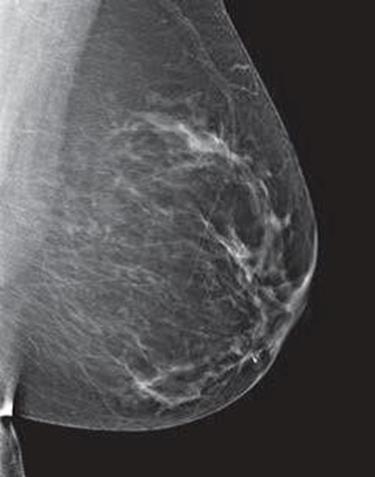

Dense breast tissue, as seen on a mammogram, has more fibrous connective tissue and glandular tissue, and less fatty tissue. It is often inherited, but menopausal hormone therapy, and low body mass index are factors associated with breast density. Dense breast tissue is a risk factor for breast cancer, and a radiologist can tell if a woman has dense breasts.

A mammogram uses X-rays (ionizing radiation) to create images of the inside of the breast to check for cancer and other conditions. It can be used for screening to detect cancer, for instance, before there’s a lump in the breast, or to assist in the diagnosis of cancer. Radiologists use mammograms to interpret, and classify breast density into four categories.